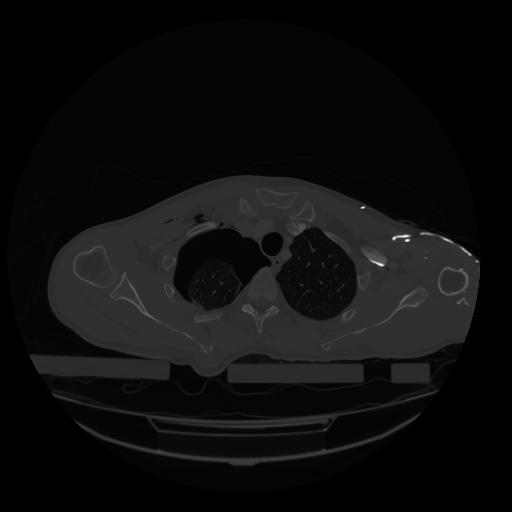

28 CUERPO,CE,Vol,2.0,CUERPO,,